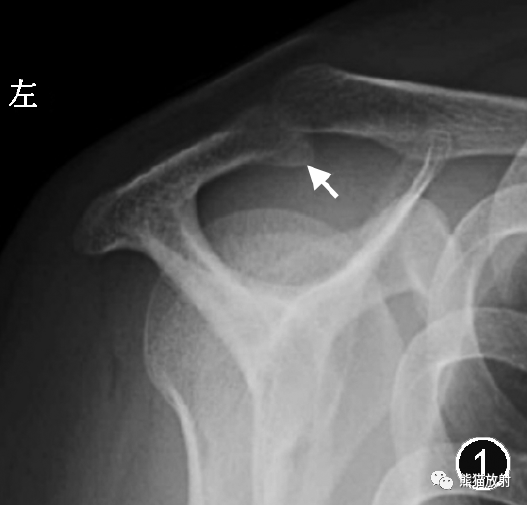

肩峰形态一般在冈上肌出口位X线片上评估(图1),也可在CT/MR的斜矢状面上评估,MR观察层面一般为肩锁关节外侧的第一幅图像。

肩峰形态分为4型,Ⅰ型为扁平形,Ⅱ型为弓形,Ⅲ型为钩形,Ⅳ型为凸面向下的反弓形,其中Ⅲ型肩峰最易引起肩峰下撞击(图2,3)。

图1 X线片评估肩峰形态。冈上肌出口位X线片示肩峰前部呈钩形(↑),为Ⅲ型肩峰。